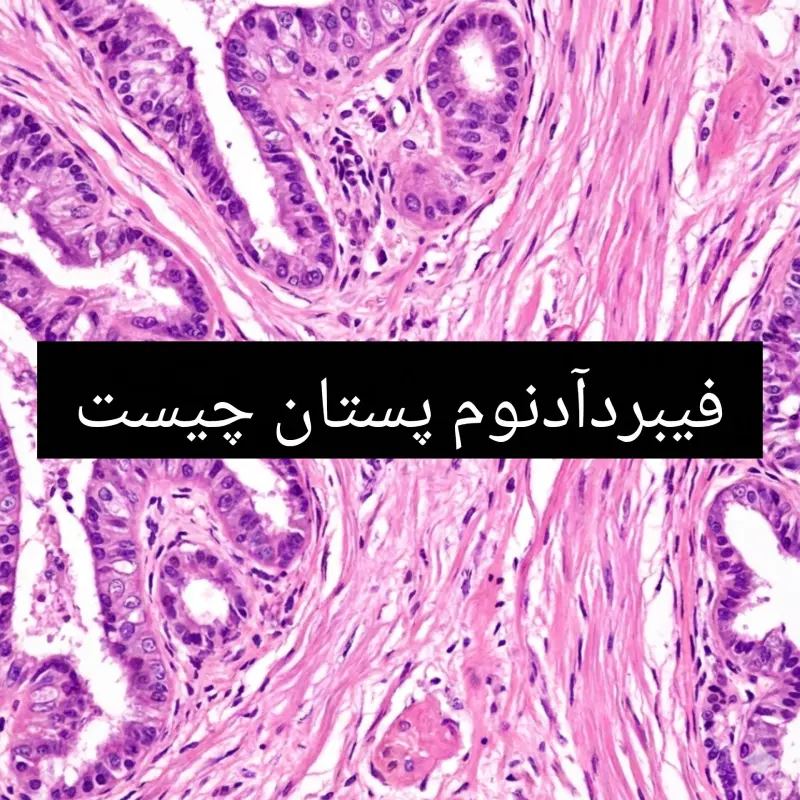

فیبرآدنوم پستان؛ شایعترین توده خوشخیم پستان

فیبرآدنوم پستان یکی از شایعترین تودههای خوشخیم پستان است که زنان جوان، بهویژه سنین ۱۵ تا ۳۵ سال را درگیر میکند. این ضایعه غیرسرطانی از ترکیب بافت غددی و بافت فیبروز پستان تشکیل شده و معمولاً بهصورت یک توده گرد، صاف و متحرک در معاینه بالینی احساس میشود. اگرچه شنیدن واژه توده پستان میتواند برای بسیاری از زنان نگرانکننده باشد، اما فیبرآدنوم در بیشتر موارد خوشخیم بوده و خطر تبدیل آن به سرطان بسیار پایین است. شناخت دقیق فیبرآدنوم، علائم آن، انواع مختلف و روشهای تشخیص بهویژه نقش مهم سونوگرافی، میتواند به کاهش اضطراب بیماران و تصمیمگیری صحیح درمانی کمک کند.

فیبرآدنوم یک تومور خوشخیم پستانی است که از رشد بیش از حد بافت غددی (آدنوماتوز) و بافت همبند (فیبروز) تشکیل میشود. علت دقیق ایجاد آن هنوز بهطور کامل مشخص نیست، اما به نظر میرسد هورمونهای زنانه بهویژه استروژن نقش مهمی در بروز و رشد آن داشته باشند. این موضوع میتواند توضیح دهد که چرا فیبرآدنومها بیشتر در سنین باروری دیده میشوند و ممکن است در دوران بارداری بزرگتر شده یا پس از یائسگی کوچک شوند.

فیبرآدنومها از نظر ویژگیهای بالینی و بافتشناسی به چند نوع تقسیم میشوند:

۲. فیبرآدنوم کمپلکس (Complex Fibroadenoma)

در این نوع، تغییرات بافتی پیچیدهتری دیده میشود، از جمله:

- کیستهای کوچک

- کلسیفیکاسیونها

- تغییرات اسکلروزان

فیبرآدنوم کمپلکس ممکن است با افزایش اندک خطر سرطان پستان همراه باشد، به همین دلیل معمولاً پیگیری دقیقتری نیاز دارد.